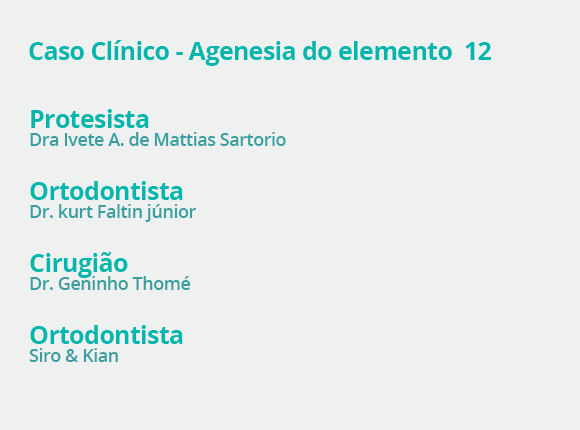

Para aproveitar o melhor da nova Odontologia, é fundamental trabalhar em equipe. Esse é o espírito do Kiyan, que conta com uma equipe altamente capacitada e especializada, liderada pelo técnico Osmar Kiyan.

Para que o seu trabalho seja um sucesso, atuamos com dois times integrados. O primeiro é formado pela equipe do laboratório, sempre alinhada para realizar o melhor trabalho laboratorial. O segundo — e mais importante — é composto por você e pelo nosso laboratório.

Esse é o verdadeiro time vencedor, pois une o melhor da Odontologia clínica e laboratorial, trabalhando pelo mesmo ideal.